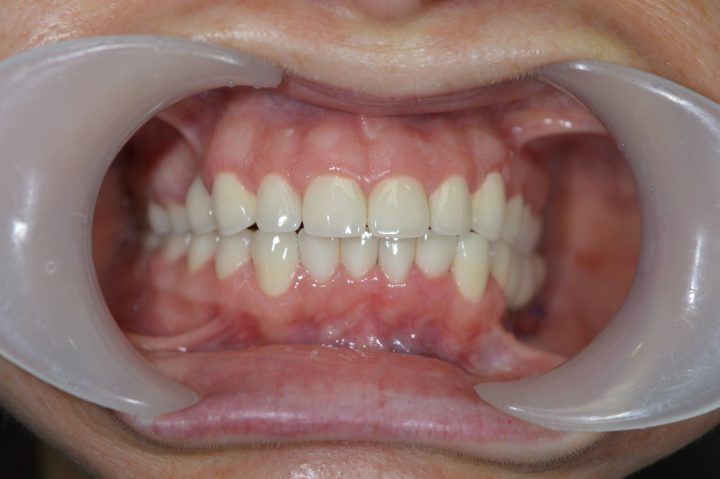

Aufgrund von der CT- Aufnahme haben wir mit dem Patienten zusammen entschieden, dass wir 4-4 Alpha Bio Implantate in Ober- und Unterkiefer einsetzen.

Die Operation dauert zweimal 1,5 Stunden lang, und wurde der provisorische Zahnersatz im Ablauf den 5 Tagen fertig. Nach der 3 Monate langen Heilungszeit wurden zwei Stegprothesen auf 4-4 Implantate befestigt.

Die Implantatprothese sichert die Stabilität für den Patienten, so konnte Daniel am Ende der Behandlung wieder Steak essen, was sein Traum war.